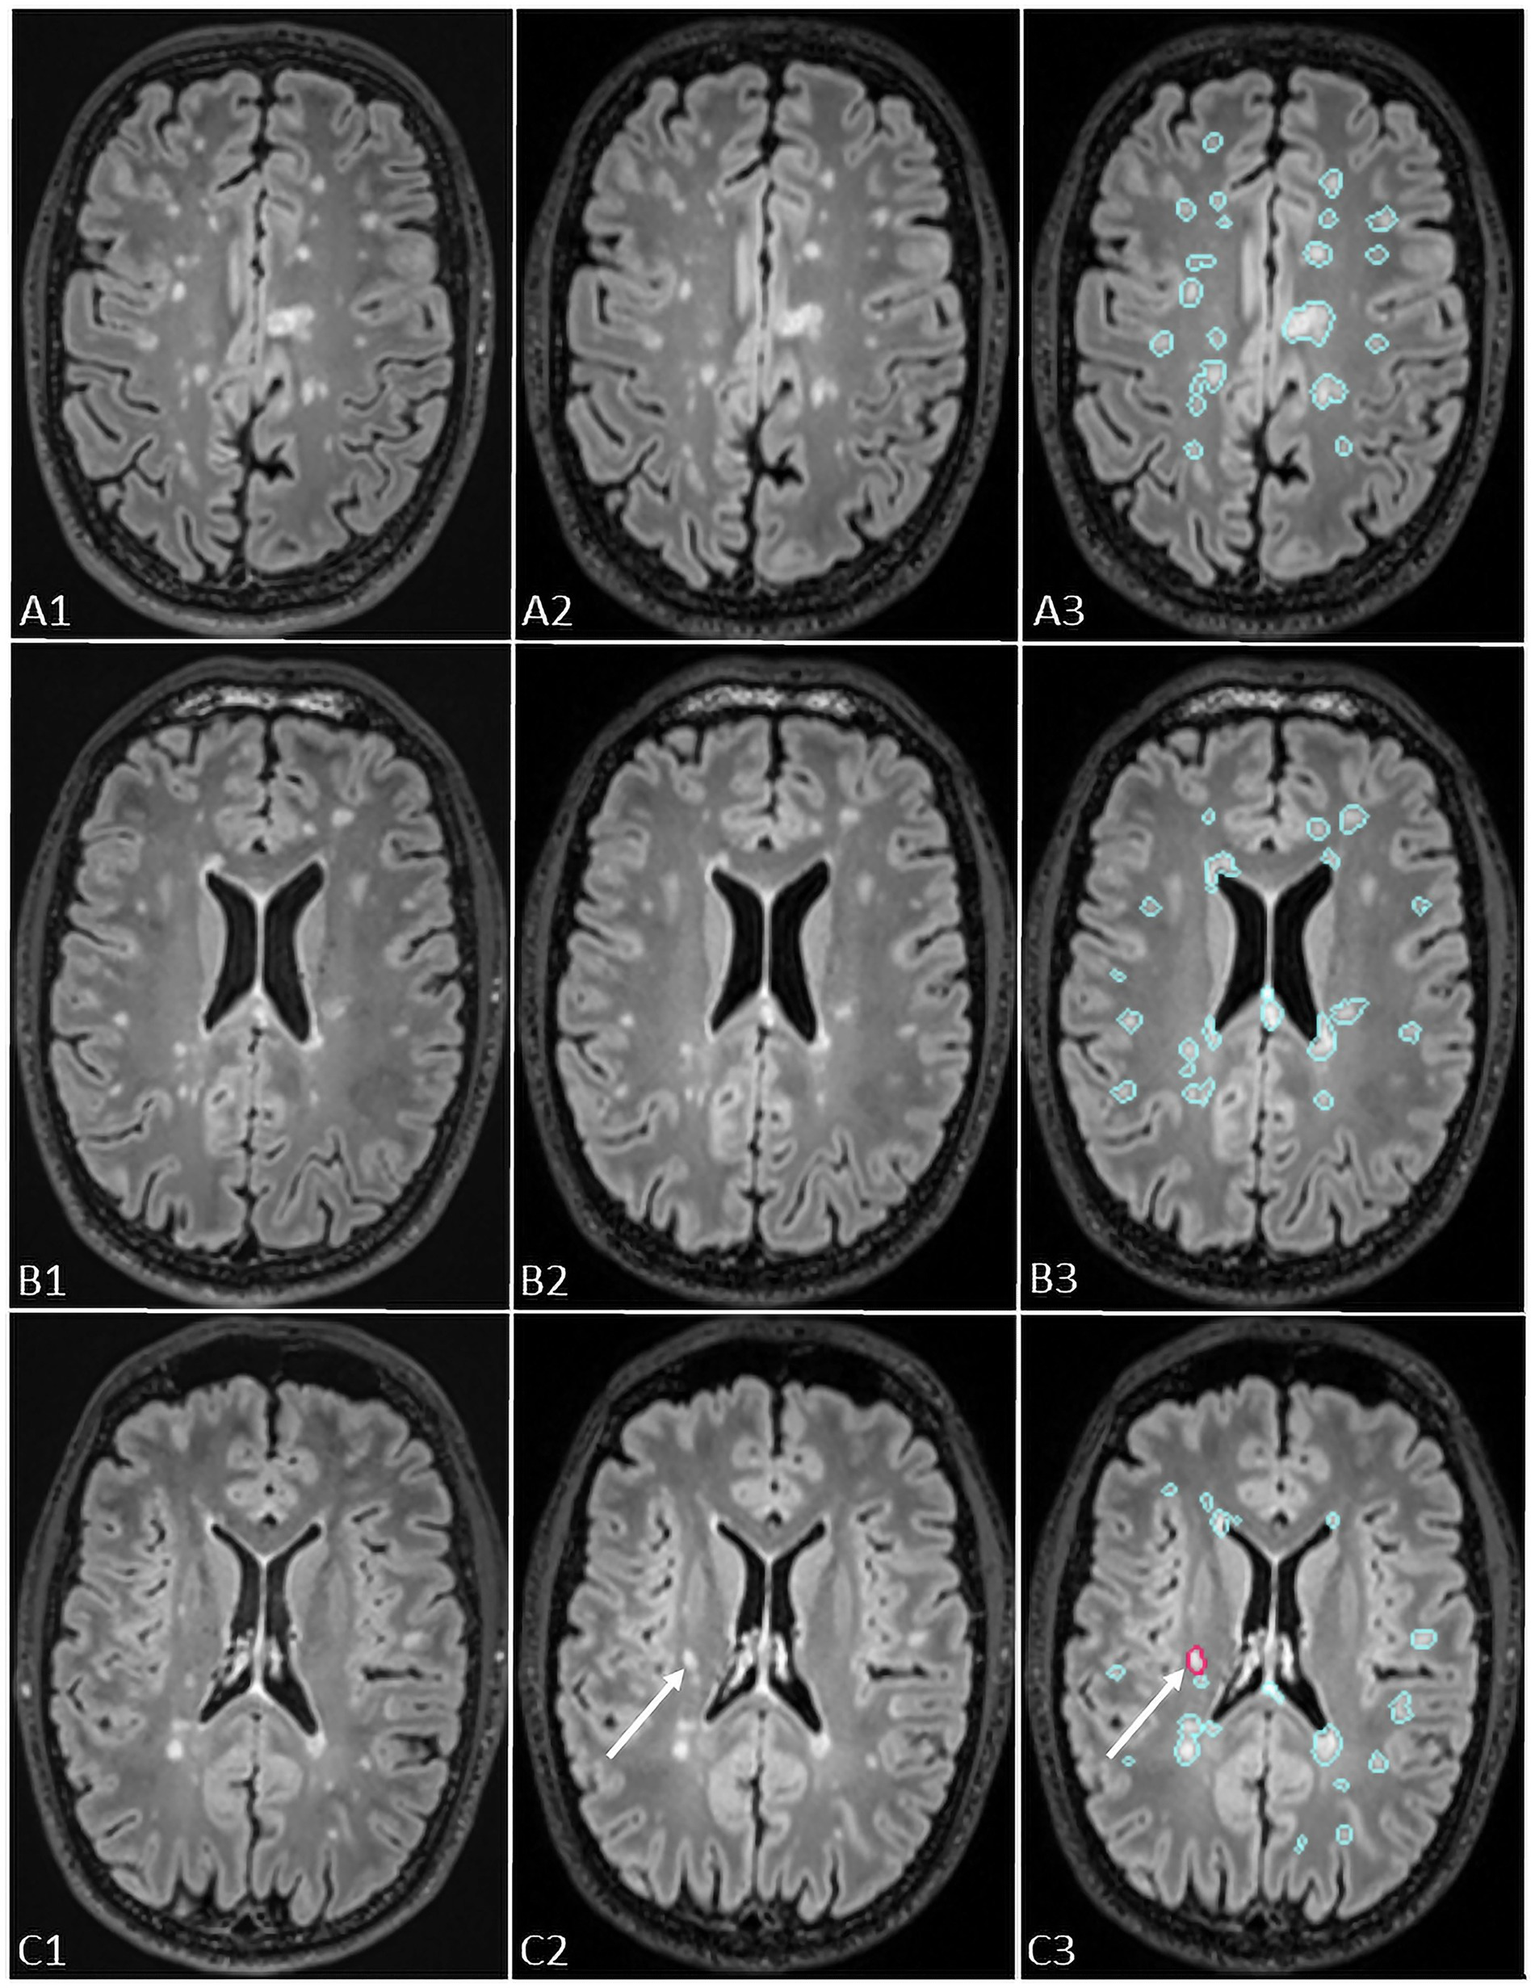

Pixyl.Neuro.MS® processes 3D T2-FLAIR sequences independent of the MRI manufacturer. The software automatically segments white matter hyperintensity lesions and quantifies lesion load by anatomical regions. When two time points are available, its longitudinal module generates a color-coded activity map (red for new lesions, blue for stable lesions, yellow for enlarging lesions) together with a quantitative report summarizing lesion number, volume, and classification (stable, new, or growing; Figure 2).

Figure 2. The figure shows representation of longitudinal evaluation of previous and new FLAIR images of a MS patient with high lesion load using Pixyl.Neuro.MS® segmentation mask. The lesions are color-coded in the segmentation mask: blue – stable lesion, red – new lesion. The white arrows in C3 indicate a new lesion detected using Pixyl.Neuro.MS®, confirmed by comparison of new (C2) and previous (C1) exams.

The ground truth reported 21 new lesions from 9 patients (Figure 3). With the use of Pixyl.Neuro.MS® software, reader 1 reported 19 true positive lesions from 9 patients, while reader 2 reported 20 true positive lesions from 8 patients. On the other hand, with the use of Jazz® software, reader 1 reported 19 true positive lesions in 8 patients, while reader 2 reported 17 true positive lesions in 7 patients. The standard report reported 8 new lesions in 2 patients.

Figure 3. The figure shows an example of the lesion (indicated by the white arrow) missed by radiological evaluation by Jazz® software, while it was detected by AI-assisted radiological report made using Pixyl.Neuro.MS® software.